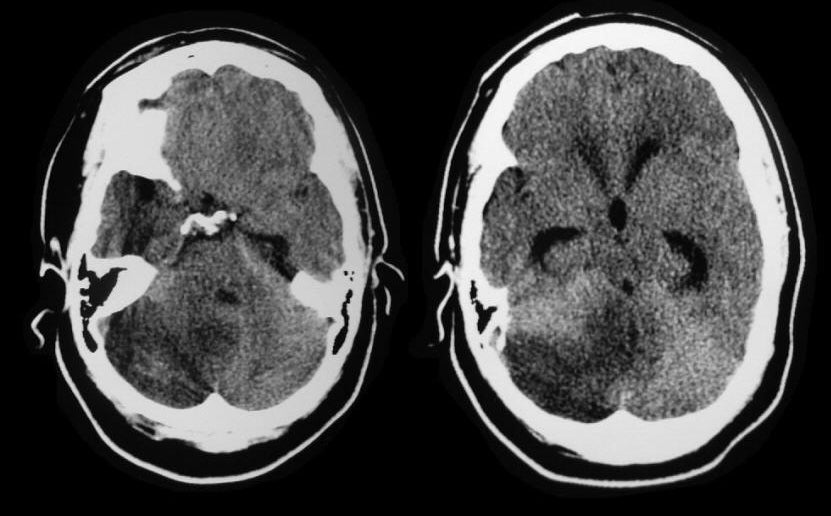

Radiology MRI Acute MCA Infarct on CT

Radiology MRI Acute MCA Infarct on CT Old Cerebellar Infarct Radiology Mri is the imaging modality of choice for diagnosing brain infarction. The overall sensitivity of ct to diagnose stroke is 64% and the specificity is 85%. Cerebellar infarcts are a subtype of acute ischemic stroke caused by the occlusion of 1 of the 3 main cerebellar branches of the vertebrobasilar arterial system: Ischemic stroke is an episode of neurological dysfunction. Old Cerebellar Infarct Radiology.